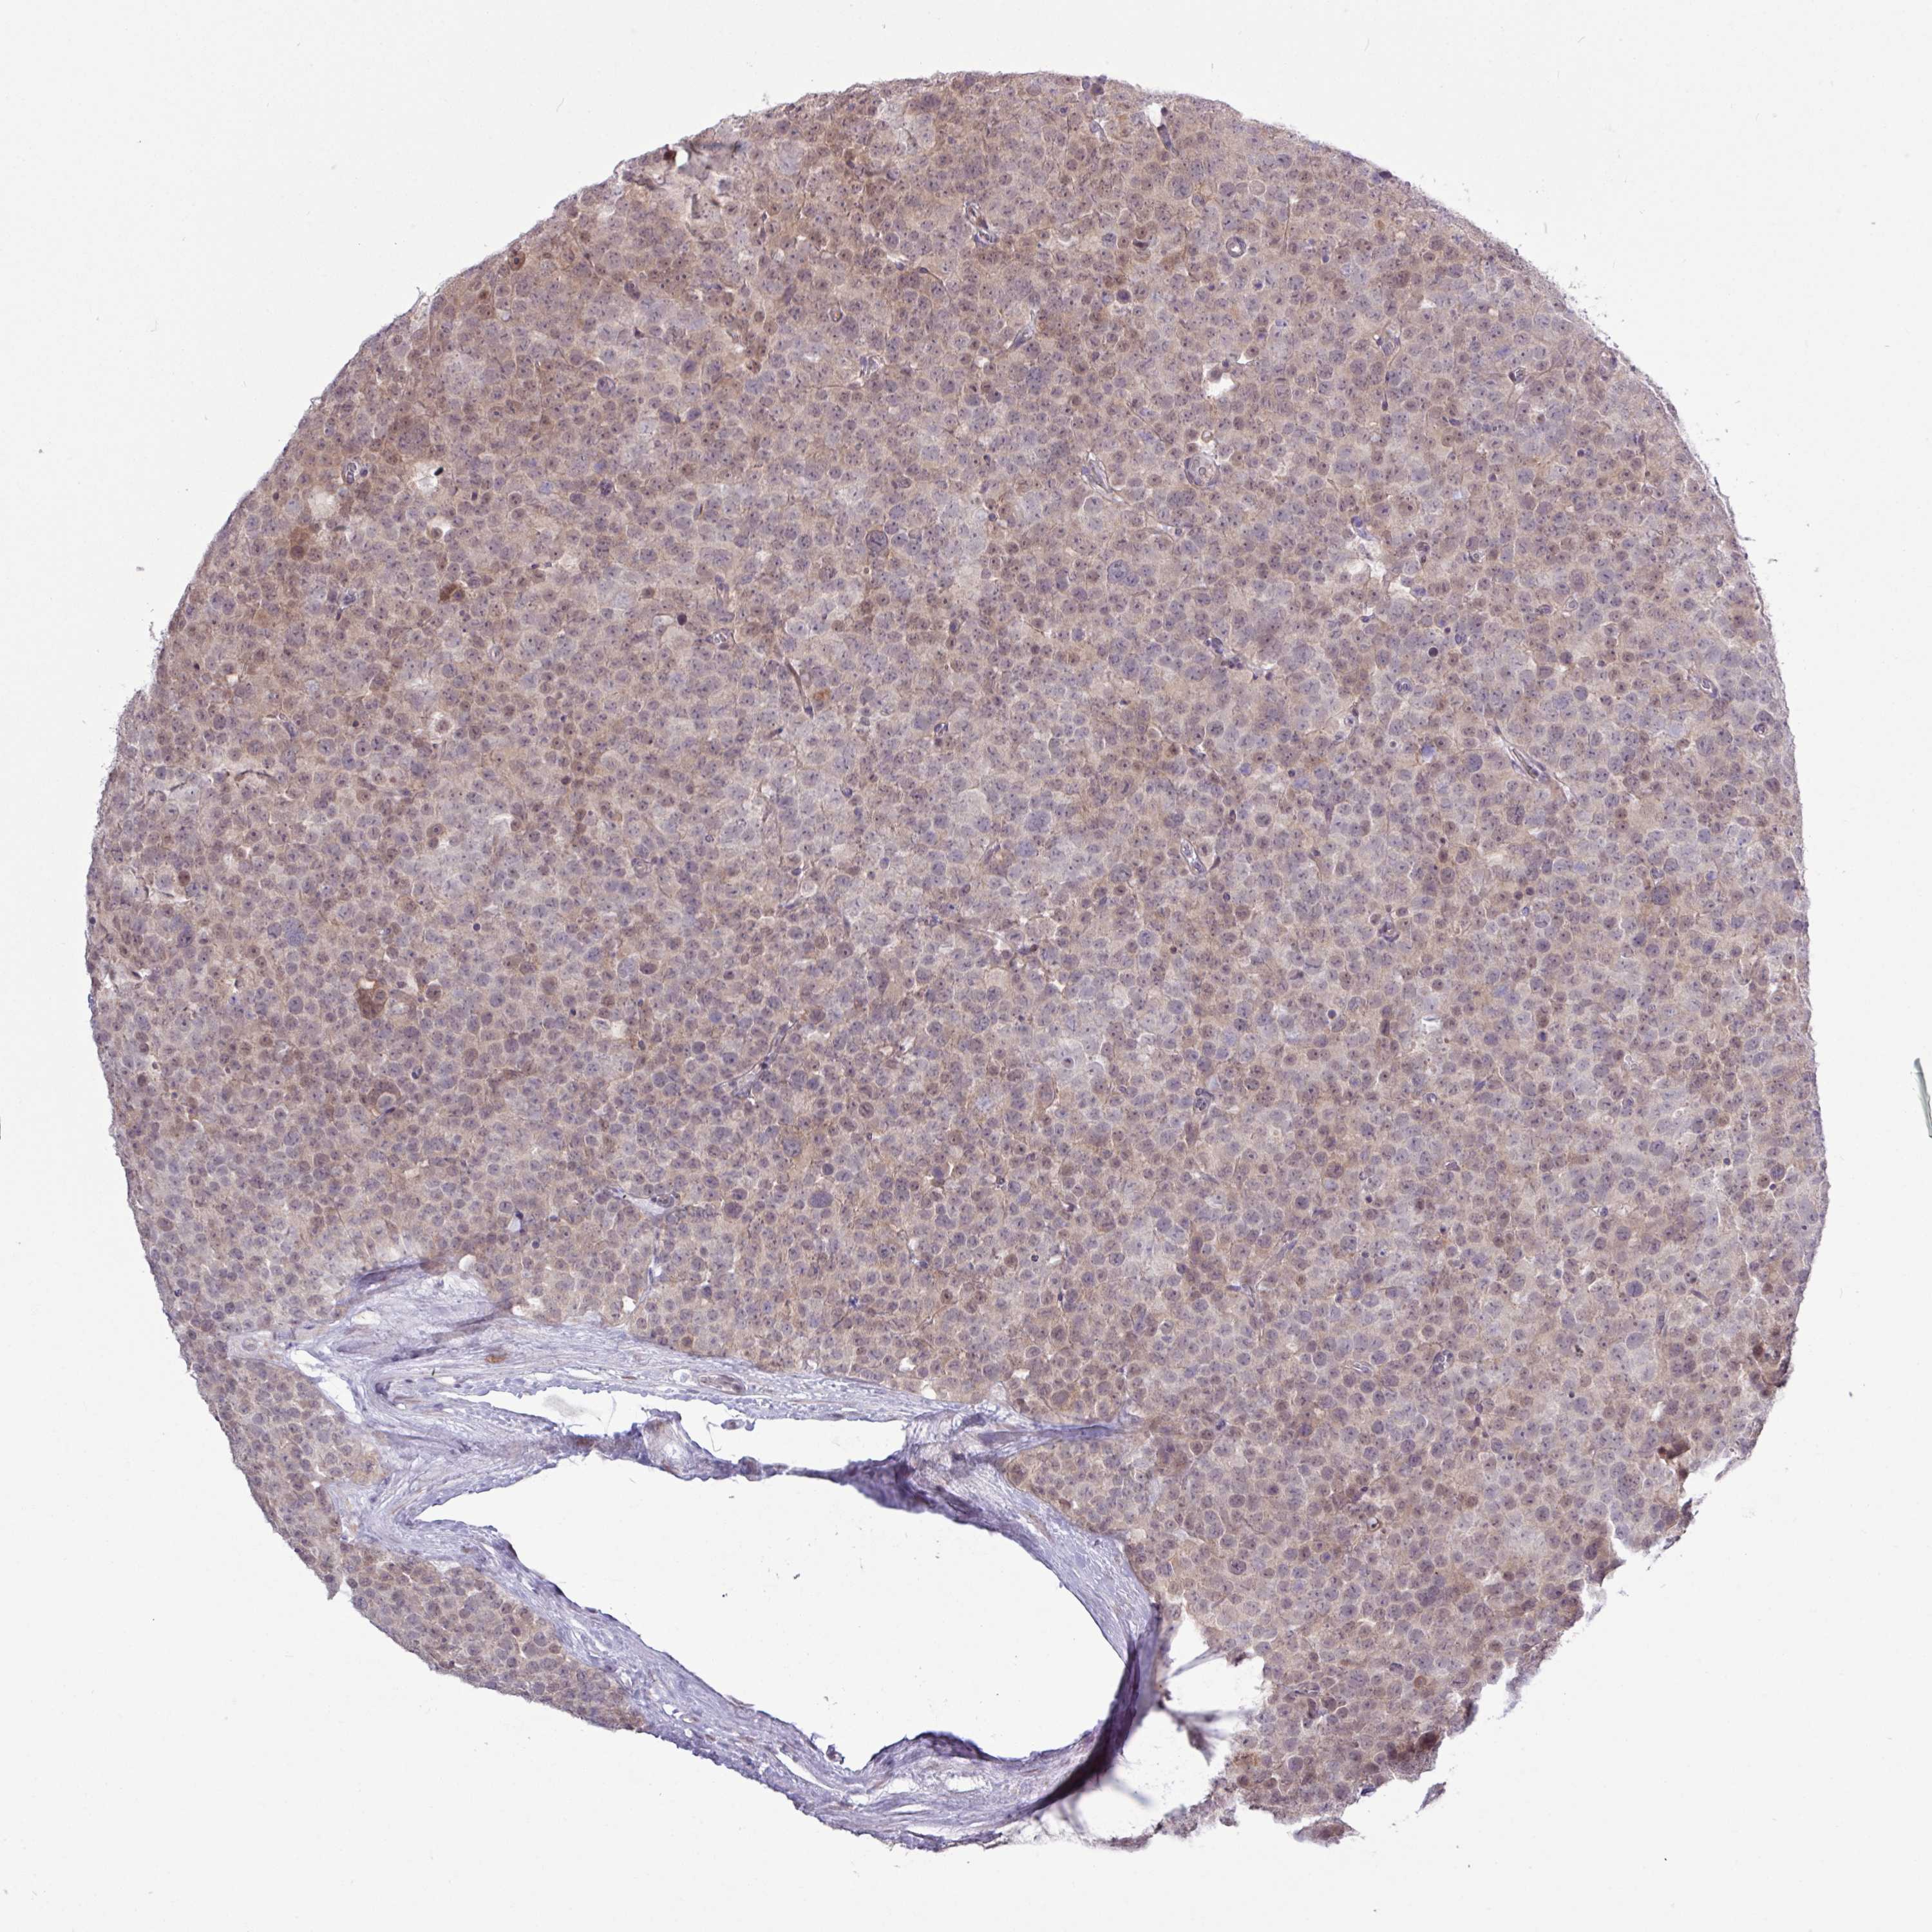

TESTIS CANCER - Protein expressioni

A mouse-over function shows sample information and annotation data. Click on an image to view it in a full screen mode. Samples can be filtered based on level of antibody staining by selecting one or several of the following categories: high, medium, low and not detected. The assay and annotation is described here.

Note that samples used for immunohistochemistry by the Human Protein Atlas do not correspond to samples in the TCGA dataset.

Antibody stainingi

Antibody staining in the annotated cell types in the current human tissue is reported as not detected, low, medium, or high, based on conventional immunohistochemistry profiling in selected tissues. This score is based on the combination of the staining intensity and fraction of stained cells.

Each image is clickable and will lead to virtual microscopy that enables deeper exploration of all samples and also displays staining intensity scores, fraction scores and subcellular localization as well as patient and tissue information for each sample.

Antibody HPA051991

Antibody HPA053174

Seminoma, NOS

Carcinoma, Embryonal, NOS